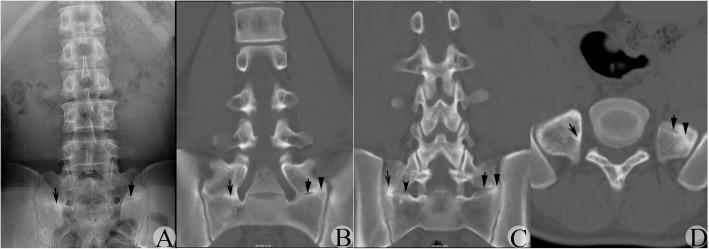

The anteroposterior view of the lumbar plain radiograph (AP-LPR) was chosen as the original and first radiographic tool to determine and classify lumbosacral transitional vertebra with morphological abnormality (MA-LSTV) according to the Castellvi classification. However, recent studies found that AP-LPR might not be sufficient to detect or classify MA-LSTV correctly. The present study aims to verify the reliability of AP-LPR on detecting and classifying MA-LSTV types, taking coronal reconstructed CT images (CT-CRIs) as the gold criteria.

A total of 298 cases were initially enrolled as suspected MA-LSTV, among which 91 cases who received CT-CRIs were enrolled into the final study group. All suspected MA-LSTVs were verified to be real MA-LSTVs by CT-CRIs. However, 35.2% of the suspected MA-LSTV types judged by AP-LPR were not consistent with the final types judged by CT-CRIs. Two suspected type IIIa and 20 suspected type IIIb MA-LSTVs were verified to be true, while 9 of 39 suspected type IIa, 9 and 3 of 17 suspected type IIb, and 11 of 13 suspected type IV MA-LSTVs were verified to truly be type IIIa, IIIb, IV and IIIb MA-LSTVs by CT-CRIs, respectively. Incomplete joint-like structure (JLS) or bony union structure (BUS) and remnants of sclerotic band (RSB) between the transverse process (TP) and sacrum were considered to be the main reasons for misclassification.

Although AP-LPR could correctly detect MA-LSTV, it could not give accurate type classification. CT-CRIs could provide detailed information between the TP and sacrum area and could be taken as the gold standard to detect and classify MA-LSTV.